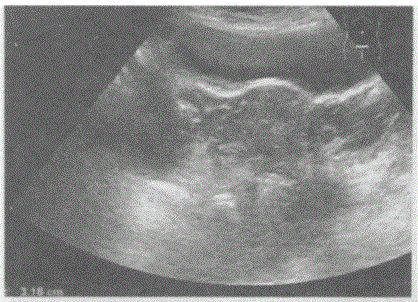

问题 临床资料:女,69岁,自诉下腹部疼痛,排便困难。 临床物理检查:右下腹可扪及一肿物,质硬,边界清,活动度好,有压痛。 超声综合描述:子宫前位,形态大小如常,肌壁回声均匀,内膜厚度0.3cm。腹、盆腔可见无回声区,上界平脐,下至耻骨联合,形态不规则,内呈网状,分隔多且厚薄不均,CDFI:分隔上可见条状血流信号,PW:呈动脉频谱,RI=0.54。

选项 A.腹盆腔多房囊性占位(卵巢癌) B.畸胎瘤 C.腹盆腔结核 D.腹盆腔包裹性积液

答案 A